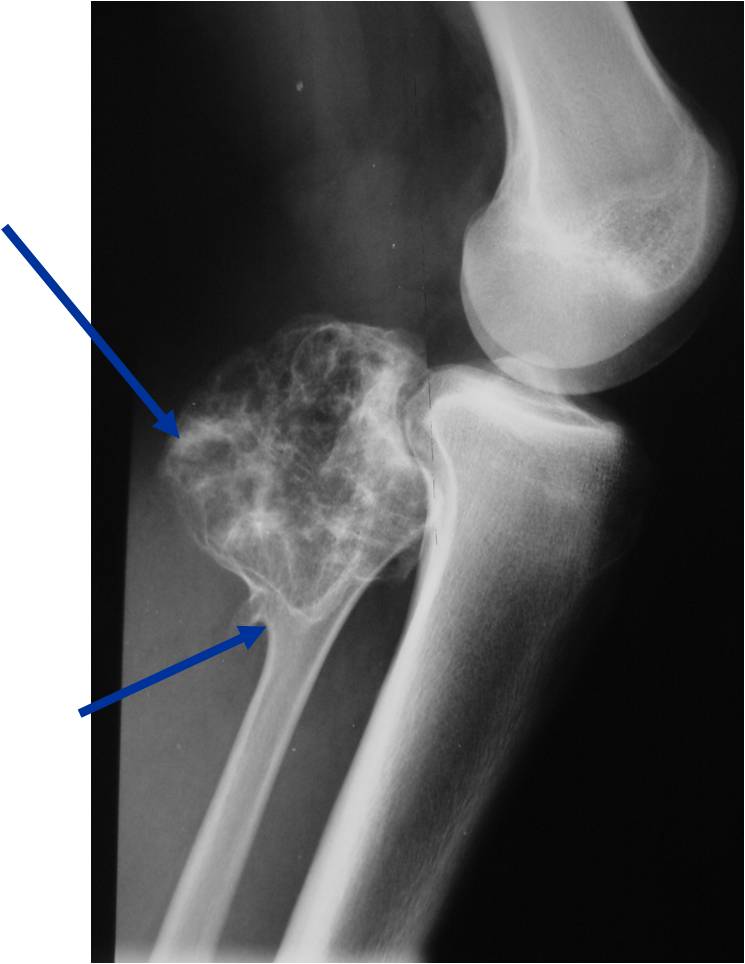

28 أكتوبر Date 28 أكتوبر، 2025 Author معمل جرين Tags التحاليل, التحاليل الطبيه, امراض العظام, جرين, حسام جاد, دكتور حسام جاد, معمل جرين نخر العظام اللاوعائي.. لما العضم “يموت” قبل أوانه! 📍 يعني إيه نخر العظام اللاوعائي؟ نخر العظام اللاوعائي أو (Avascular Necrosis) ه...